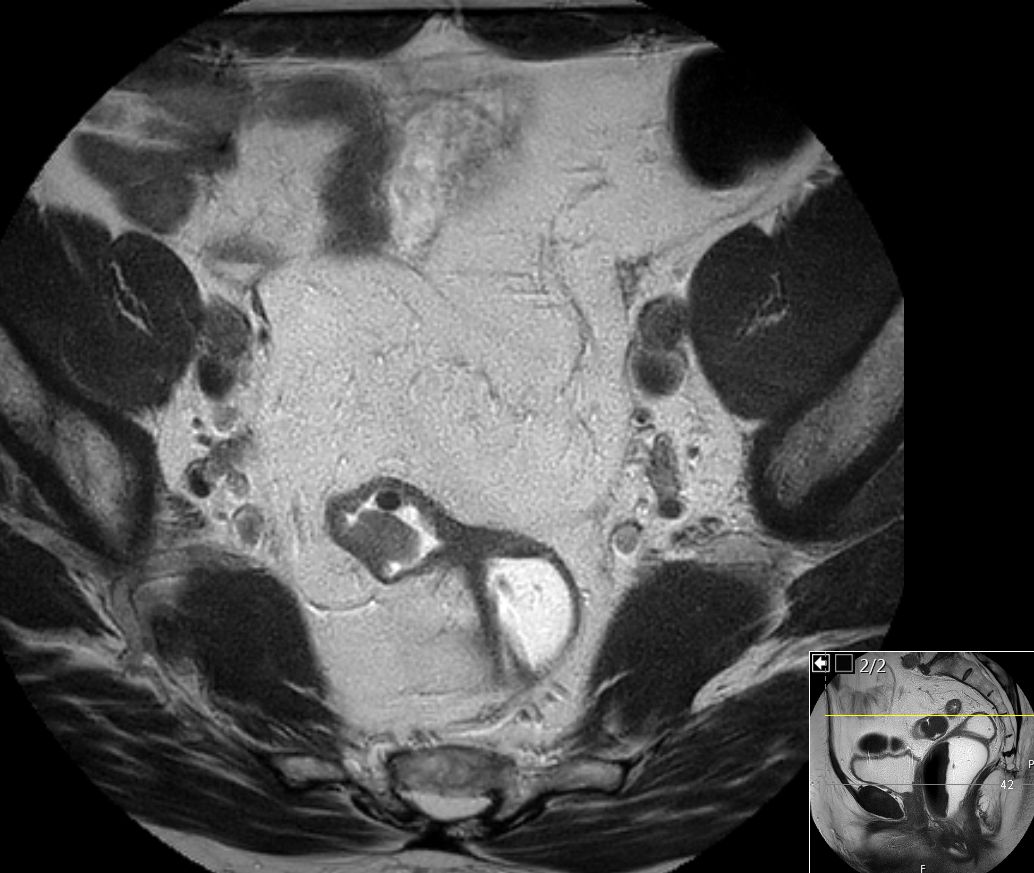

| MRT: T4-Tumor | 67-jähriger Mann mit stenosierendem Rektumkarzinom T4 N1 M1hep. Der Tumor strahlt in alle Richtungen und erreicht links die Beckenwand und dorsal das Steißbein. Kontakt zur Samenblase. Blasenwand dorsal verdickt. Großer LK an der Iliaca externa rechts.![]() | |||